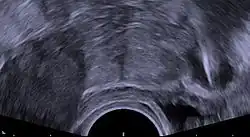

Transvaginal ultrasonography showing a perforated copper IUD as a hyperechoic (rendered as bright) line at right, 30 mm (1.2 in) away from the uterus at left. The IUD is surrounded by a hypoechoic (dark) foreign-body granuloma.

Regardless of the IUD type, some potential side effects are similar for all IUDs. Some of these side effects include bleeding pattern changes, expulsion, and pelvic inflammatory disease (especially in the first 21 days after insertion). The occurrence of IUD migration is rare, with reported rates in medical literature varying between 0.1% and 0.9%. However, when migration occurs, it can lead to serious complications such as uterine perforation and, in rare cases, bladder perforation. Bladder perforation, while uncommon (affecting only 2% of displaced IUDs), can result in symptoms like urinary frequency, hematuria, and stone formation, often necessitating surgical intervention for removal.[82] Regular monitoring and imaging, such as ultrasound or CT scans, are recommended to detect such complications early and ensure timely treatment. A small probability of pregnancy remains after IUD insertion, and when it occurs, there is a greater risk of ectopic pregnancy.[83]